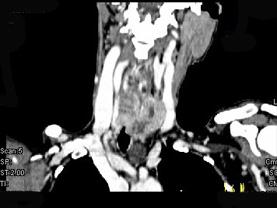

问题 女,50岁,左下颈部扪及一质硬、表面高低不平的包块,约半年,肿块逐渐增大,现感吞咽困难。如图所示CT诊断为()

选项 A.甲状腺癌 B.食管癌 C.喉癌 D.甲状腺原发淋巴瘤 E.颈部神经鞘瘤

答案 A